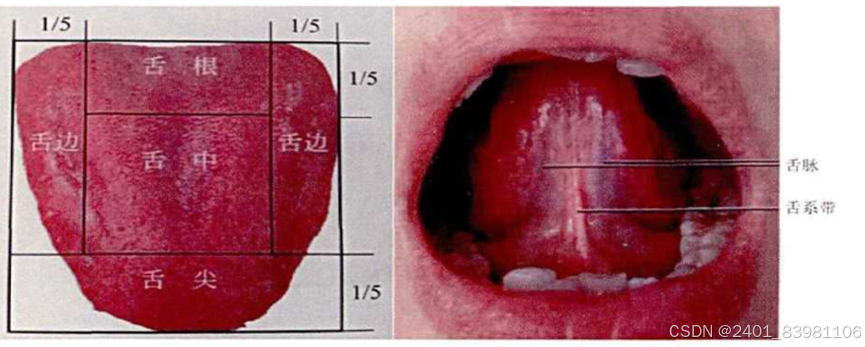

### 舌象分割:

一般是将舌像细分为不同的区域,使得舌像变得更加容易理解、更有意义的技术和过程,

### 舌象特征提取:

1. **形状特征**:

- 轮廓提取:利用边缘检测算法获取舌部轮廓信息。